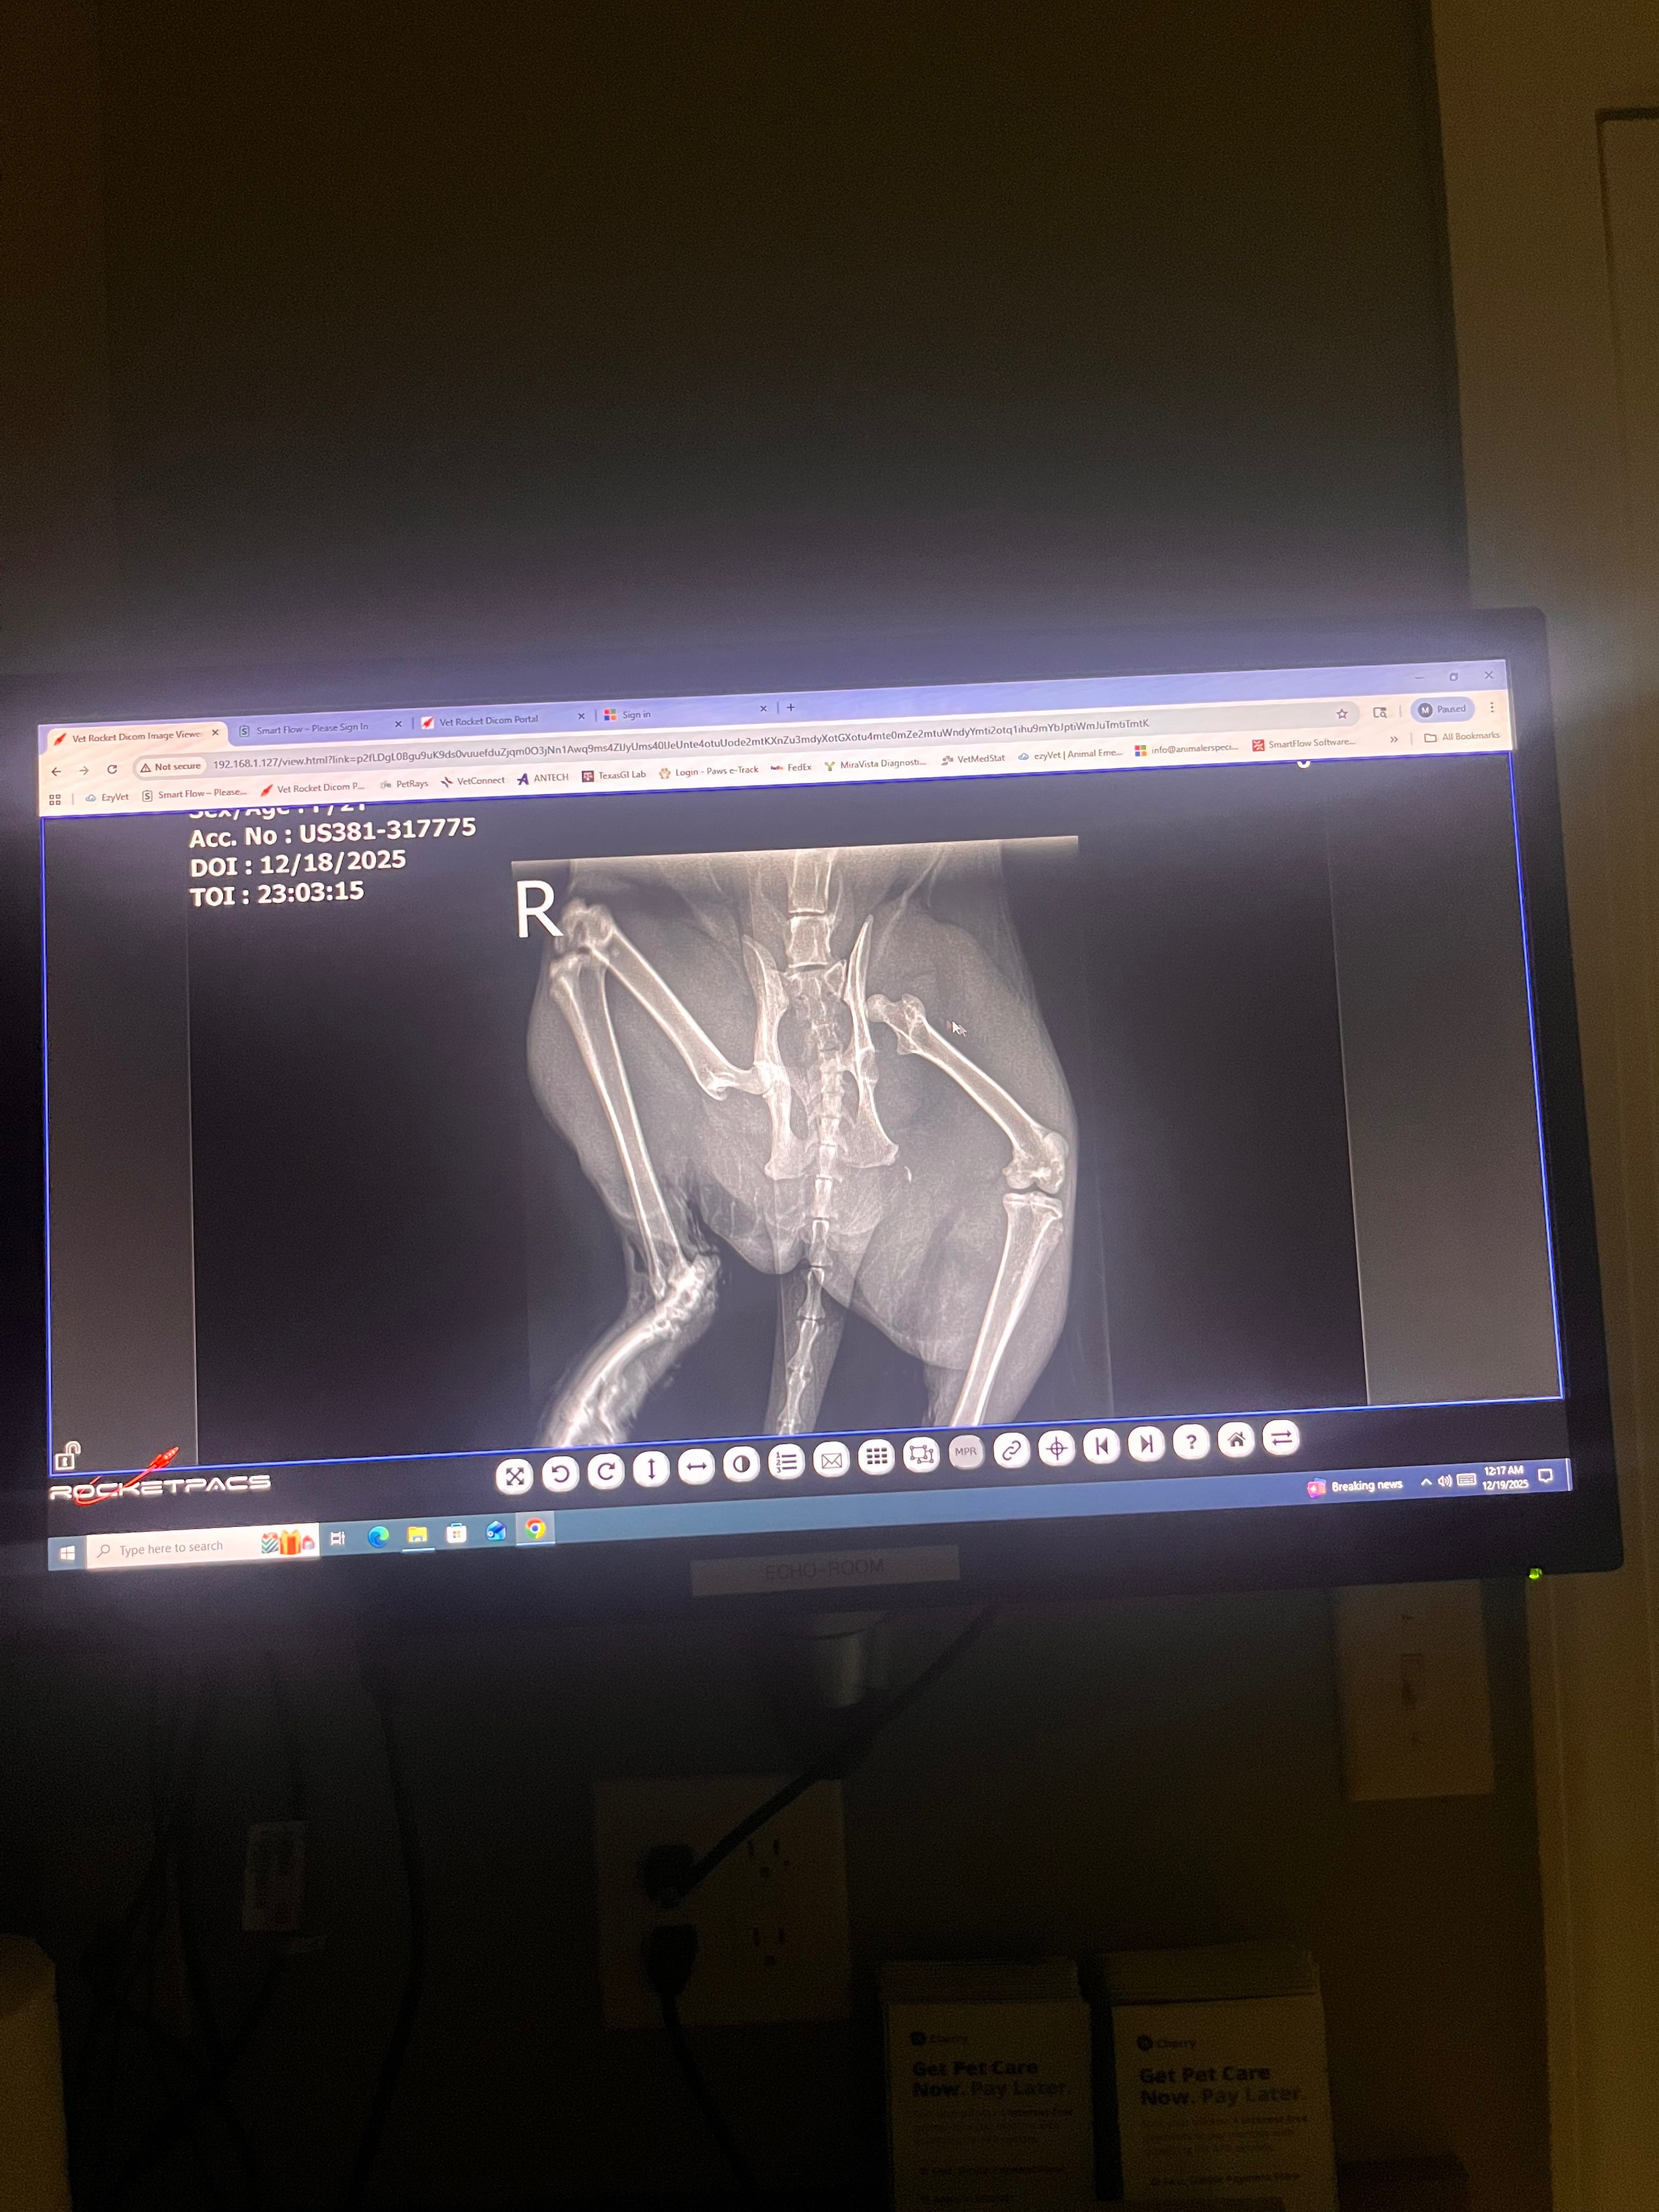

We walked outside to see our cat, laying in the rain, freezing with her back legs completely skinned with their bones sticking out. We rushed her to the nearest clinic and were charged $1006.79 just for admission and x-rays. After this, the radiologists discovered her hip is completely out of place and needs a procedure that is going to cost $5k. Her right leg is also broken and will have to be amputated, which is another $3k. Our family is scraping by as it is, with not even a fraction of that amount in our bank account. This is the cat that we loves and care about so much. With Christmas coming up, it would be excruciatingly painful to have to go through the debts or have to euthanize her. We are begging that you can help Pete, who we call Petey-Pete, get money for her surgeries.